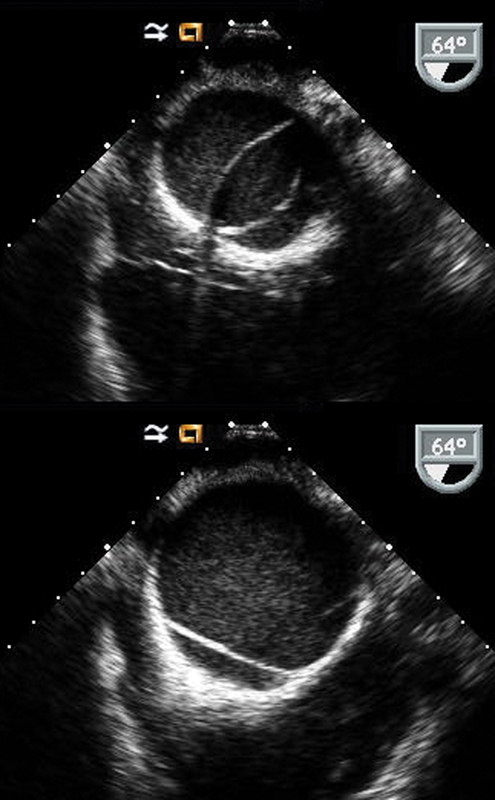

فحوصات تشخيصية لبعض امراض القلب والشرايين التاجية